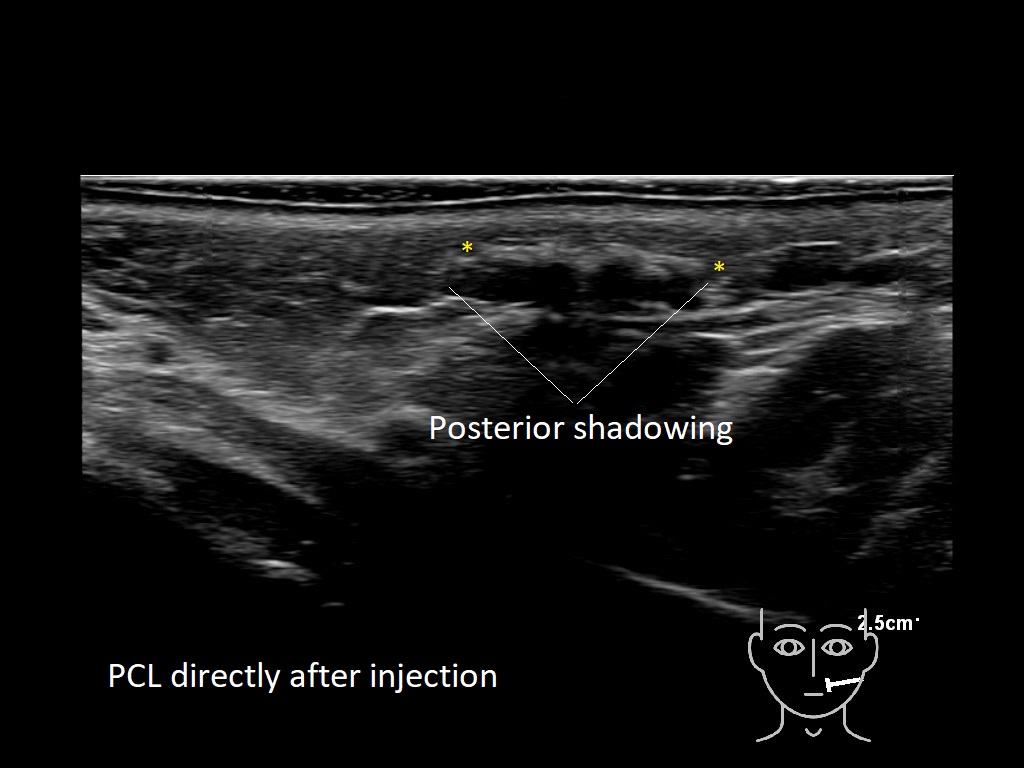

Fillers

Draw in the second image below where the fillers are located. To check if your answer is correct, swipe the first image to the right.

PCL 0